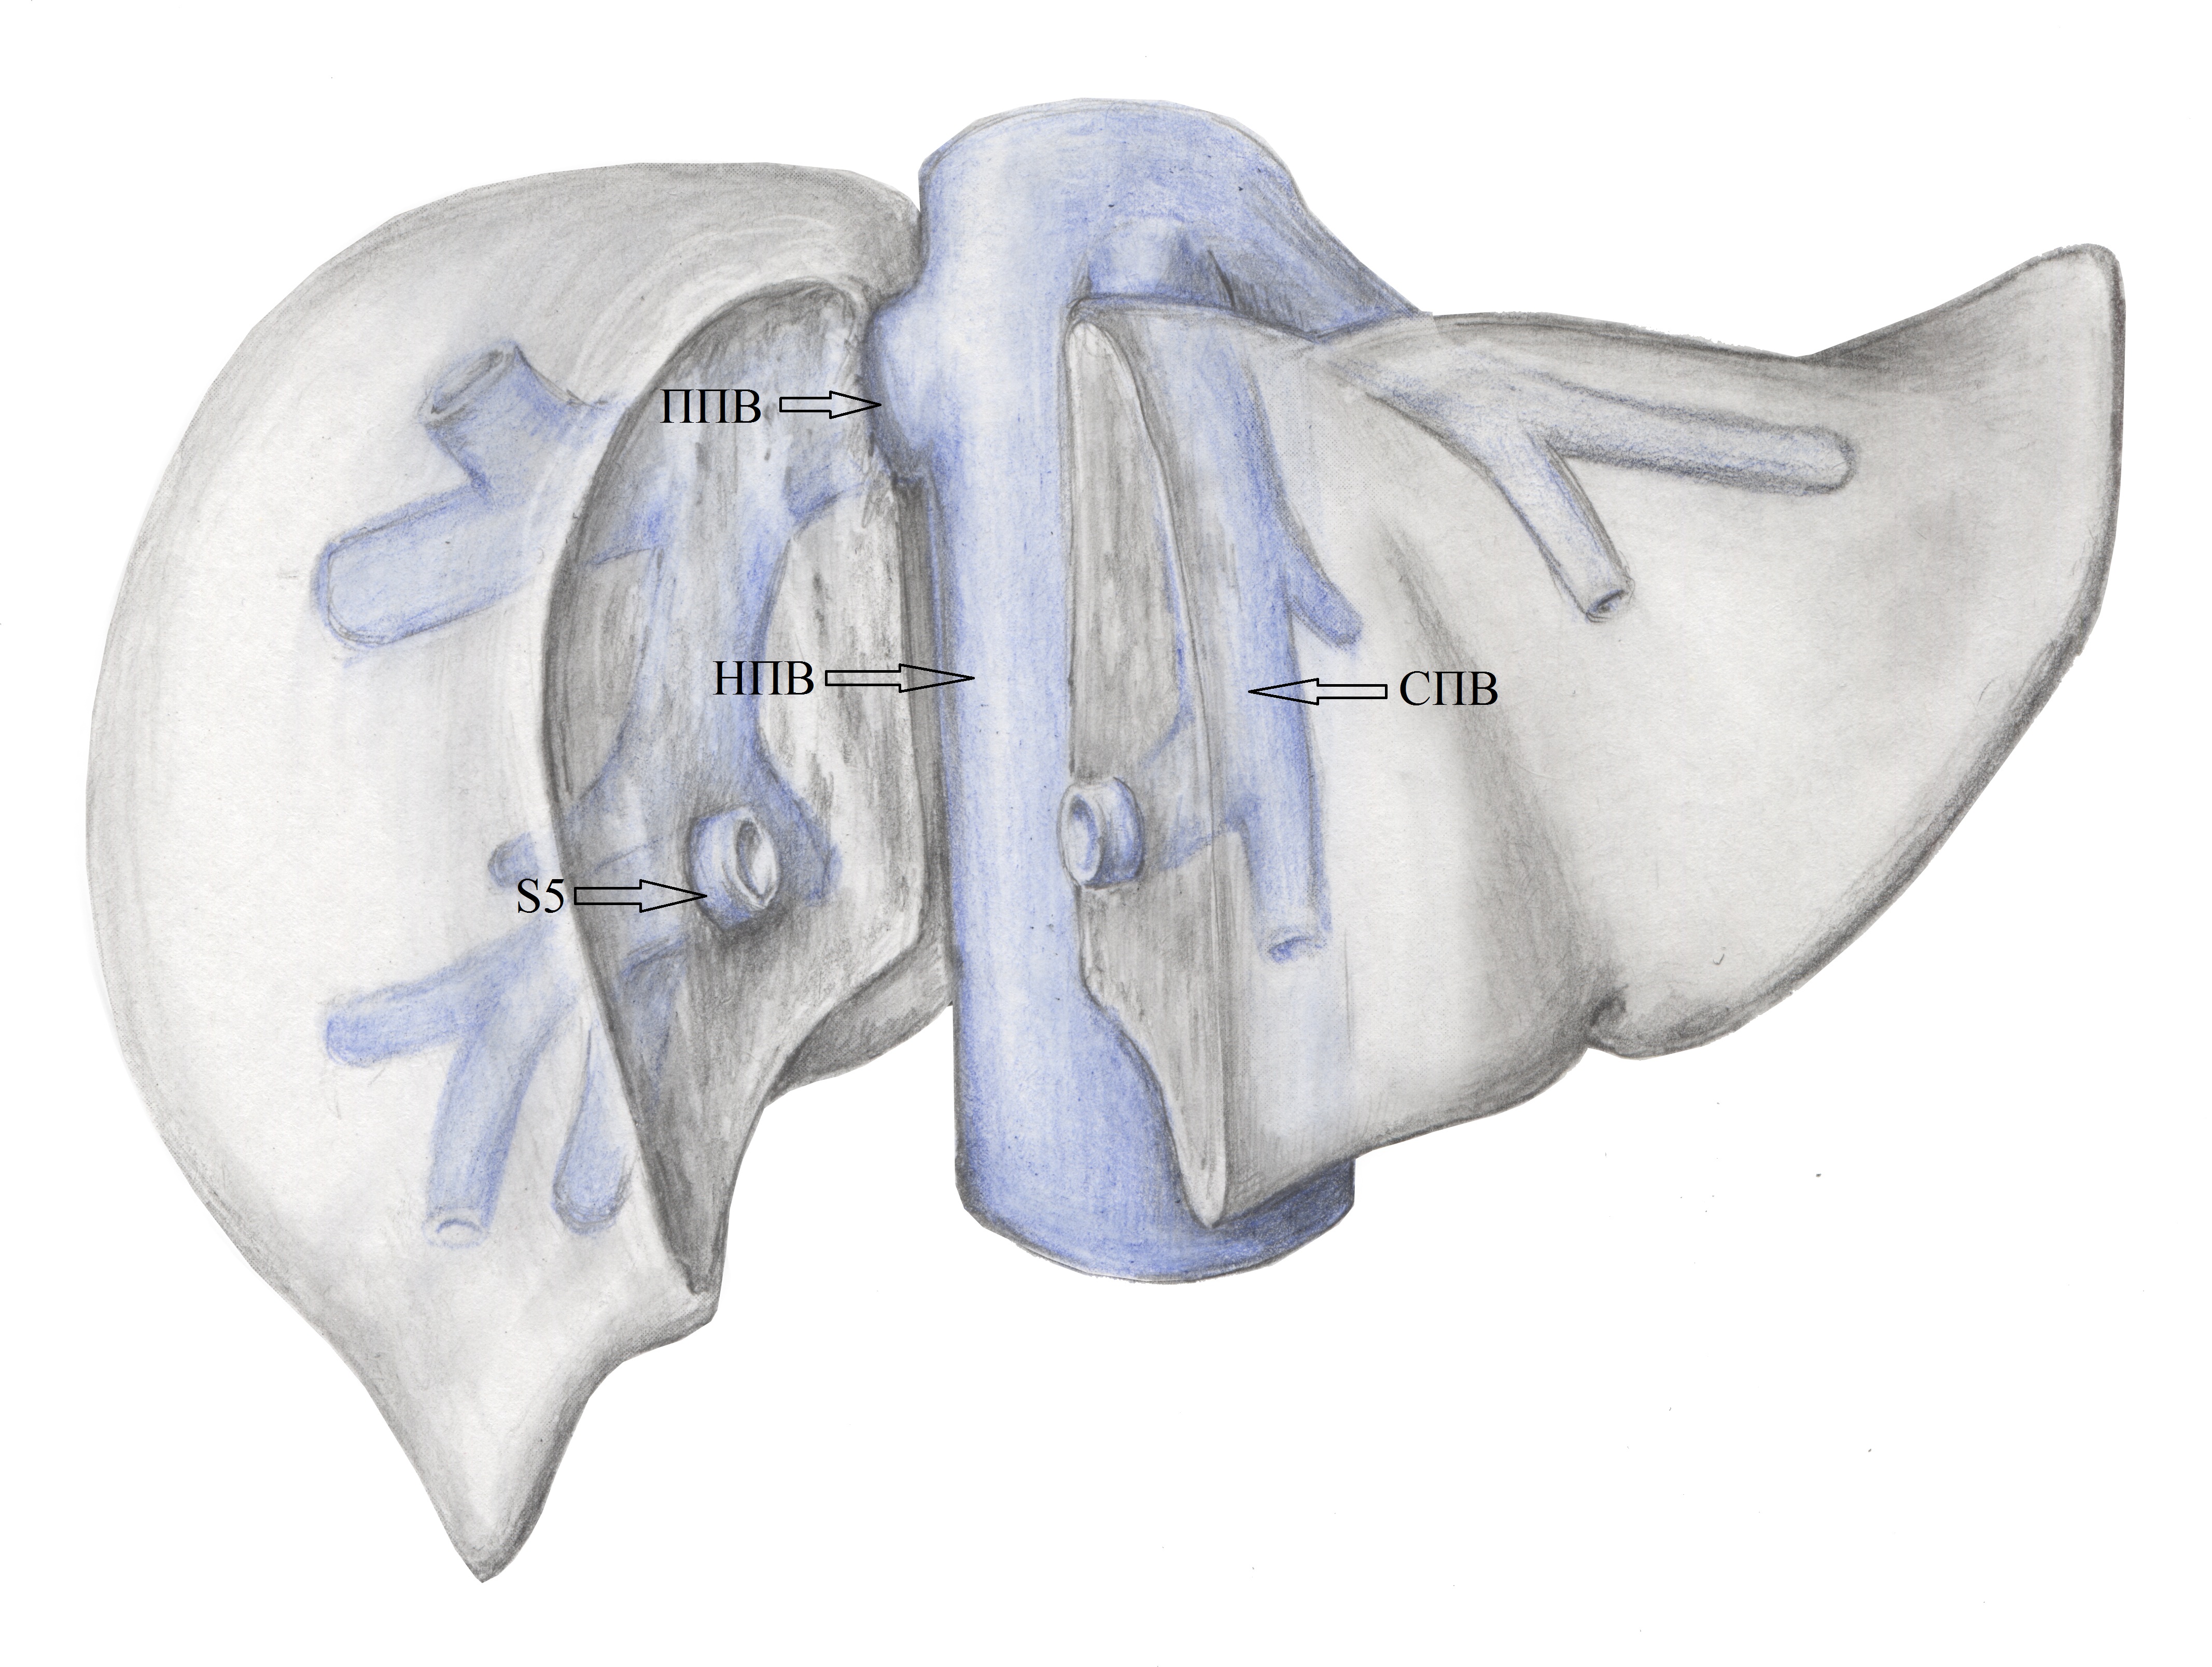

5. Тип B (схема). | |

| Тема | ||

| Тип | Исследовательские инструменты | |

Посмотреть

(1MB)

|

Метаданные ▾ | |